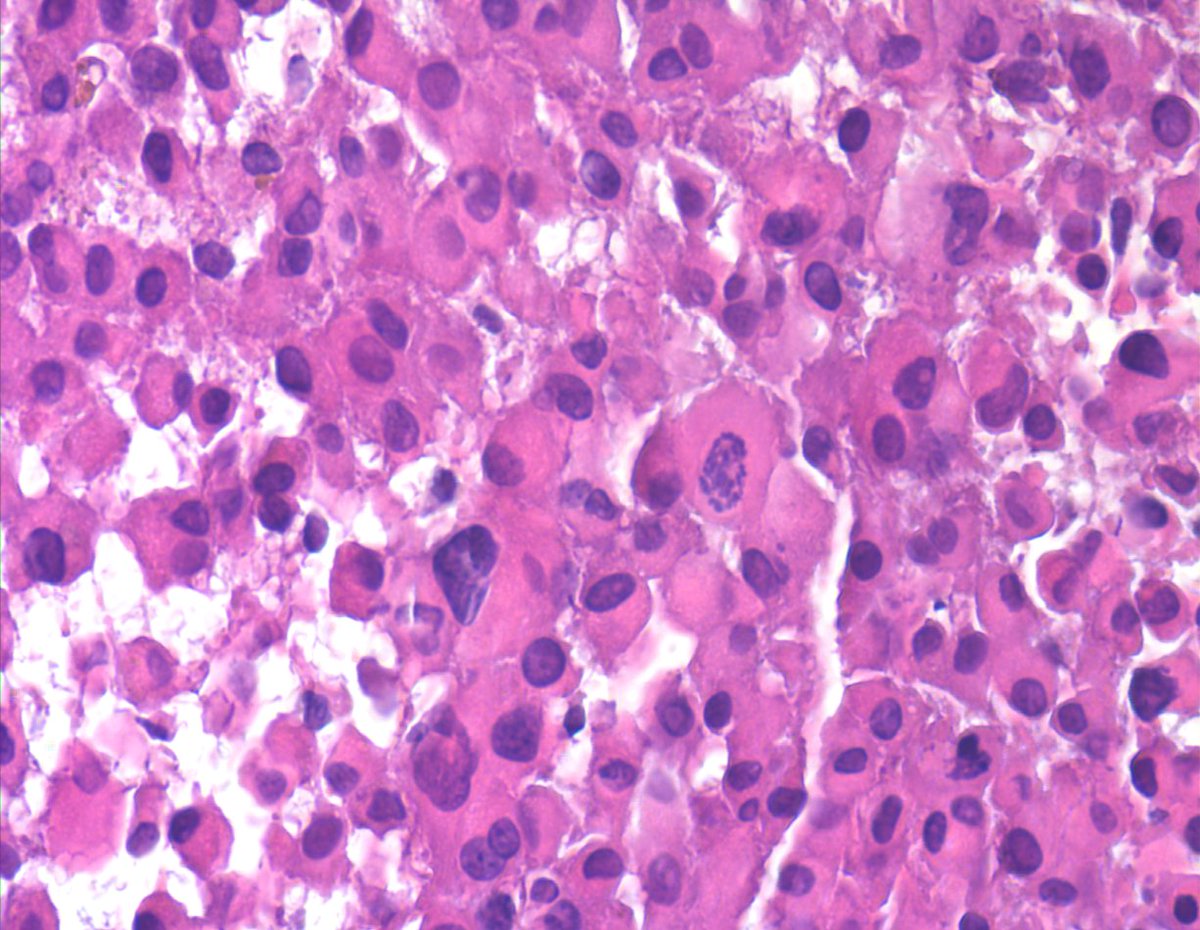

Soft tissue mass. NOT a met melanoma, Carcinoma or Mesothelioma. Most of you may only see 1-2 cases of this rare sarcoma in a lifetime of FNA practice. "Proximal-type Epithelioid Sarcoma - Epithelioid to rhabdoid cells, binucleation, macronucloli  and eosinophilic cytoplasm (CB).